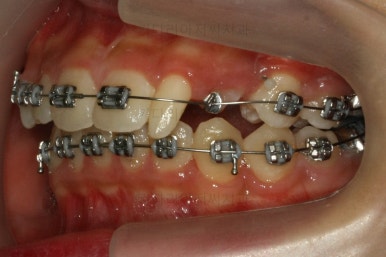

처음 장치를 부착한 이 후 8개월이 흐른 시점이네요. 꽤나 오랫동안 천천히 송곳니를 가지런하게 해줘요.

치료 10개월째의 모습입니다.